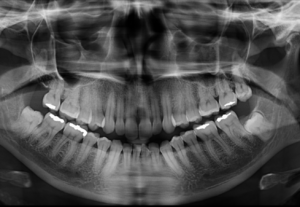

En la radiografía panorámica (Figura 1), se aprecia imagen radiolucida unilocular proyectada sobre zona anterior del maxilar superior, de limites definidos, bordes corticalizados.

Radiografia Panorámica